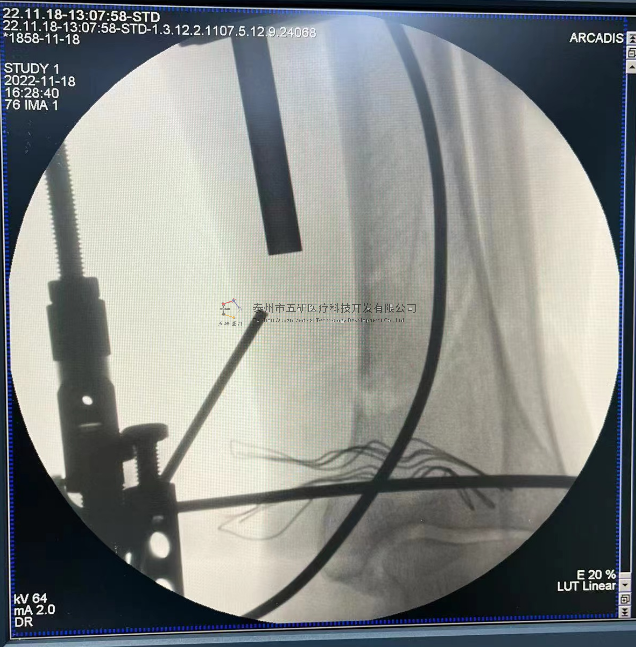

【治療后影像】

6.png

【手術(shù)資料】

8.png